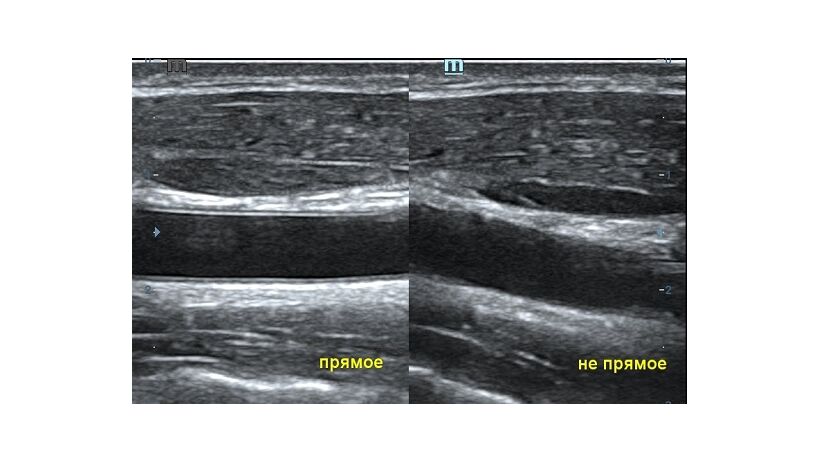

Оптимизация изображения происходит и за счет постобработки. Наиболее часто используемый инструмент - общее усиление (Gain). Усиление делает изображение «ярче», но чем сильнее усиление, тем меньше различия между структурами. Также используются усиление по времени (TGC) и усиление по длине (LGC), которые позволяют изменять отображение на экране послойно, позволяя подсветить гипоэхогенные участки, или, наоборот, снизить визуально эхогенность слишком ярких моментов. Данный вид оптимизации требует много времени, для упрощения работы доктора на приборах Mindray внедрена система автоматической оптимизации - iTouch.